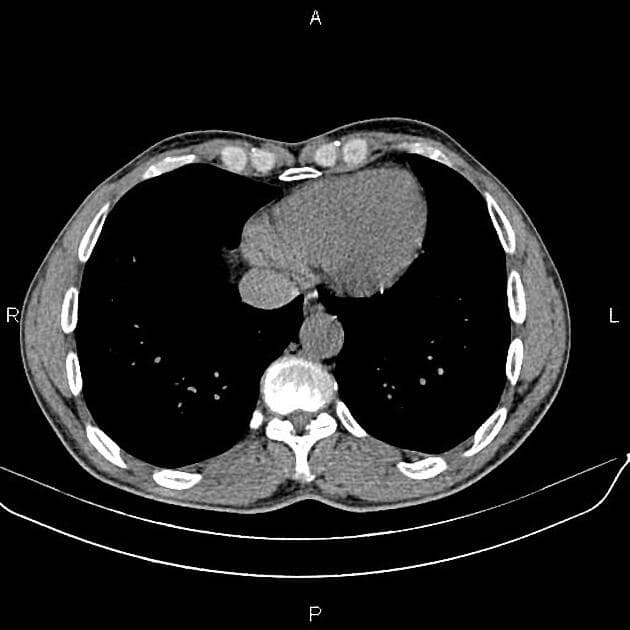

Nhiều tổn thương nội sọ bắt thuốc (enhancing intracerebral lesions), chủ yếu ở vùng hố sau.

Các tổn thương có dạng đặc, thay vì dạng nang với nốt đặc thành nang (cystic with a solid mural nodule).

Khối u thần kinh đặc trưng là u mạch máu nhân dạng tế bào (hemangioblastoma), có thể xuất hiện ở não hoặc tủy sống.

- "U mạch máu trong VHL thường đa ổ và có thể xảy ra ở tiểu não, thân não và tủy sống."